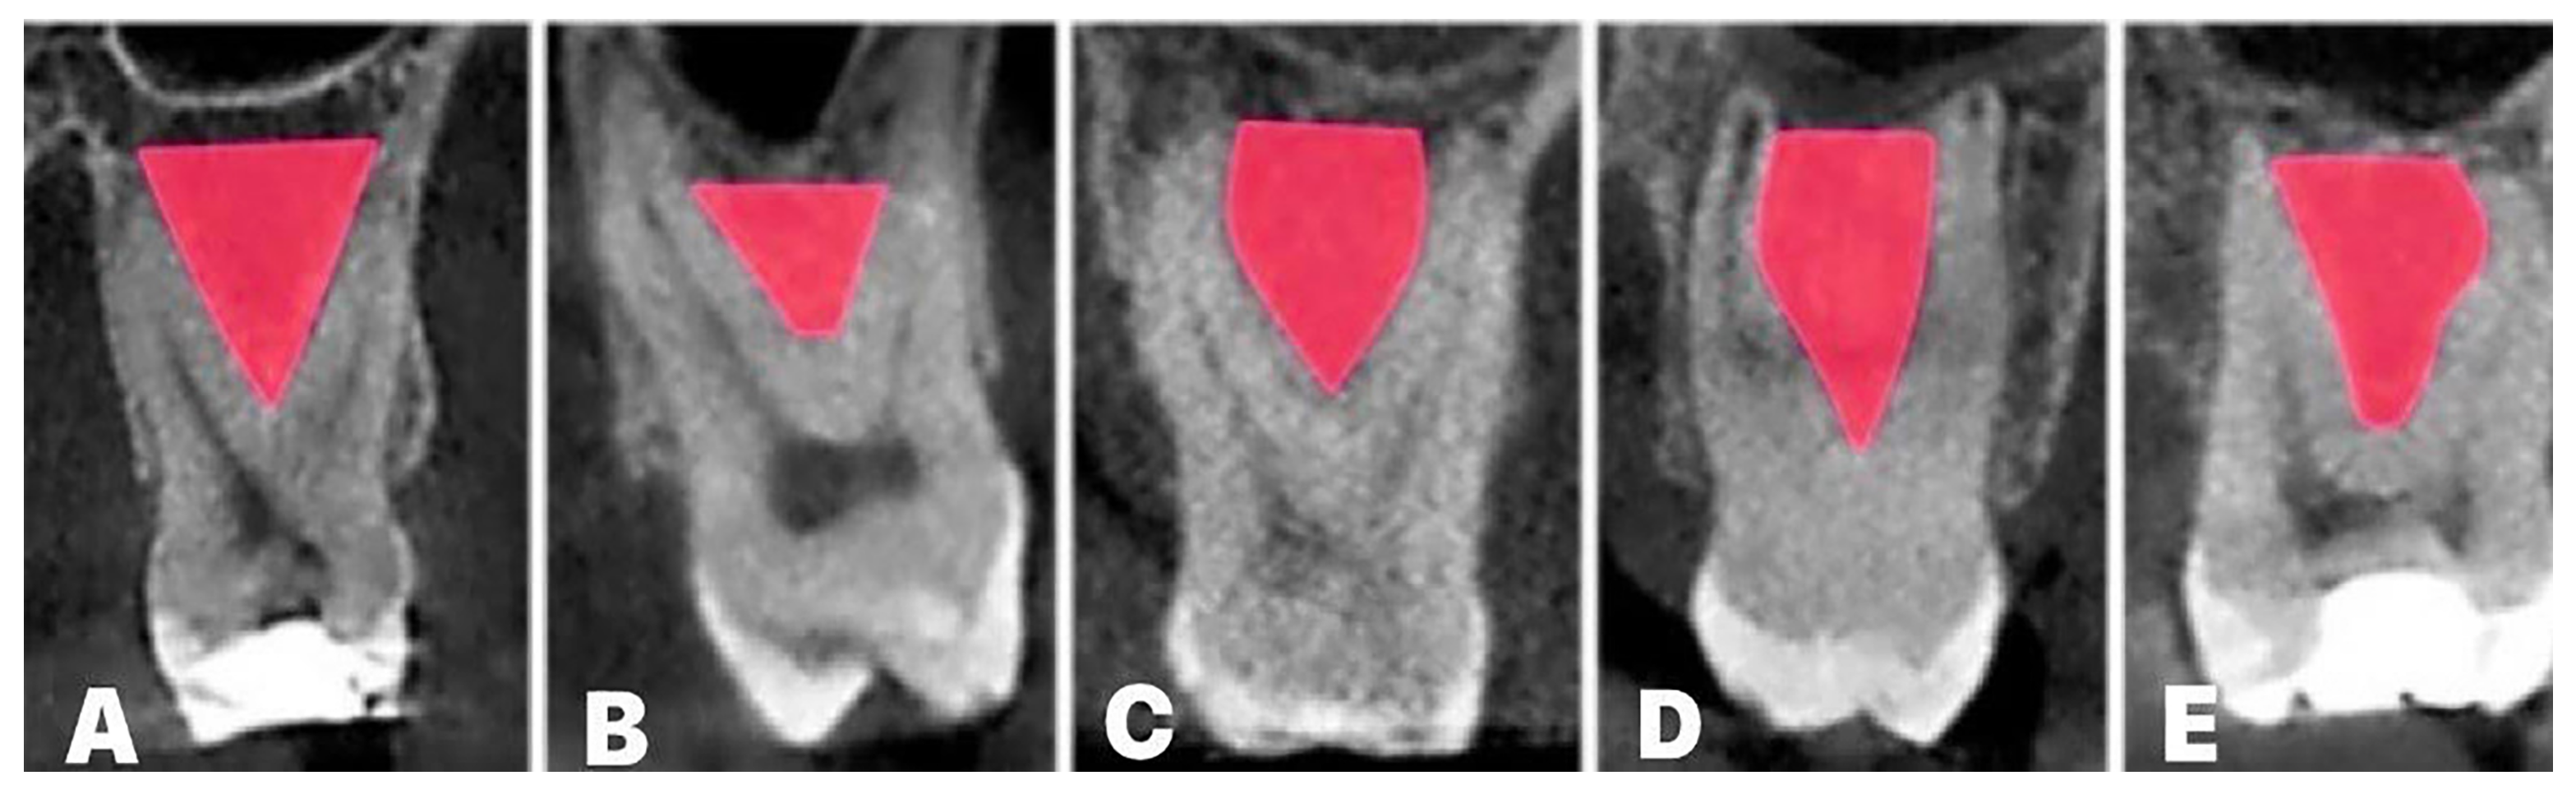

- Pavlovic, Z.R.; Milanovic, P.; Vasiljevic, M.; Jovicic, N.; Arnaut, A.; Colic, D.; Petrovic, M.; Stevanovic, M.; Selakovic, D.; Rosic, G. Assessment of Maxillary Molars Interradicular Septum Morphological Characteristics as Criteria for Ideal Immediate Implant Placement—The Advantages of Cone Beam Computed Tomography Analysis. Diagnostics 2022, 12, 1010. [Google Scholar] [CrossRef] [PubMed]

- Milenkovic, J.; Vasiljevic, M.; Jovicic, N.; Milovanovic, D.; Selakovic, D.; Rosic, G. Criteria for the Classification of the Interradicular Septum Shape in Maxillary Molars with Clinical Importance for Prosthetic-Driven Immediate Implant Placement. Diagnostics 2022, 12, 1432. [Google Scholar] [CrossRef] [PubMed]

- Bleyan, S.; Gaspar, J.; Huwais, S.; Schwimer, C.; Mazor, Z.; Mendes, J.J.; Neiva, R. Molar Septum Expansion with Osseodensification for Immediate Implant Placement, Retrospective Multicenter Study with Up-to-5-Year Follow-Up, Introducing a New Molar Socket Classification. J. Funct. Biomater. 2021, 12, 66. [Google Scholar] [CrossRef] [PubMed]

- Smith, R.B.; Tarnow, D.P. Classification of molar extraction sites for immediate dental implant placement: Technical note. Int. J. Oral Maxillofac. Implants 2013, 28, 911–916. [Google Scholar] [CrossRef] [PubMed]

- Agostinelli, C.; Agostinelli, A.; Berardini, M.; Trisi, P. Anatomical and Radiologic Evaluation of the Dimensions of Upper Molar Alveoli. Implant Dent. 2018, 27, 171–176. [Google Scholar] [CrossRef] [PubMed]

- Padhye, N.; Shirsekar, V. Tomographic evaluation of mandibular molar alveolar bone for immediate implant placement—A retrospective cross-sectional study. Clin. Oral Implants Res. 2019, 30, 265. [Google Scholar] [CrossRef]

- Nunes, L.S.; Bornstein, M.M.; Sendi, P.; Buser, D. Anatomical characteristics and dimensions of edentulous sites in the posterior maxillae of patients referred for implant therapy. Int. J. Periodontics Restor. Dent. 2013, 33, 337–345. [Google Scholar] [CrossRef] [PubMed]

- Iglesia-Puig, M.A.; Solana, F.J.; Holtzclaw, D.; Toscano, N. Immediate Implant Considerations for Interradicular Bone in Maxillary Molars: Case Reports. J. Implant Adv. Clin. Dent. 2012, 4, 19–31. [Google Scholar]

- Pavlovic, Z.R.; Petrovic, M. Morphological Characteristics of Maxillary Molars Interradicular Septum and Clinical Implications—What Do We Know So Far? Serb. J. Exp. Clin. Res. 2022. [CrossRef]

- Sayed, A.J.; Shaikh, S.S.; Shaikh, S.Y.; Hussain, M.A. Interradicular bone dimensions in primary stability of immediate molar implants—A cone beam computed tomography retrospective analysis. Saudi Dent. J. 2021, 33, 1091–1097. [Google Scholar] [CrossRef] [PubMed]